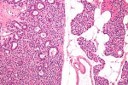

Figure 4.MEN1 syndrome demonstrating a parathyroid adenoma with encapsulation and glandular proliferation13.

Figure 5.MEN1 syndrome demonstrating goitrous enlargement of thyroid gland with colloid impaction13.